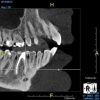

(8.) An original finding of a small lesion on the mesial root of tooth No. 30 was not accompanied by any outward symptoms; therefore, the patient delayed pursuing treatment. When a follow-up CBCT scan was acquired 6 years later, the easy-to-visualize increase in the dimensions of the lesion motivated the patient to elect a treatment plan.

Figure 8

(9.) An original finding of a small lesion on the mesial root of tooth No. 30 was not accompanied by any outward symptoms; therefore, the patient delayed pursuing treatment. When a follow-up CBCT scan was acquired 6 years later, the easy-to-visualize increase in the dimensions of the lesion motivated the patient to elect a treatment plan.

Figure 9

Identifying the shape and location of the roots of teeth to be removed is critical to performing safe exodontia. Some clinicians virtually deconstruct teeth using CBCT images prior to actually sectioning and removing them. Being able to recognize pathoses and differentiate affected structures from normal structures is key in deciding what the treatment should be and when that treatment should be initiated (Figure 8 through Figure 10). The arena of the oral surgeon is larger than that of many general practitioners, involving the sinuses and condyles and other considerations in and around the entire mandible and maxilla. Certain fractures and other conditions that some general practitioners feel uncomfortable treating are often referred for evaluation and treatment by an oral surgeon. Because of this, oral surgeons require the most accurate and complete diagnostic information available. The American Academy of Oral and Maxillofacial Radiology recommends that "cross-sectional imaging be used for the assessment of all dental implant sites" and has stated that "CBCT is the imaging method of choice for gaining this information."18